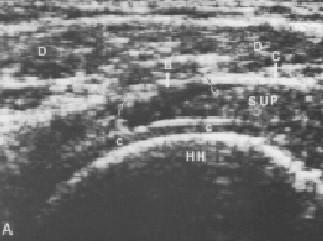

ECOGRAFIA

INDICACIONES DE ECOGRAFIA • Visualización de la Bursa subacromial • Tendones del manguito Rotador • Porción larga del bíceps • Labrum glenoideo

ULTRASONOGRAFIA

• SIGNOS ECOGRAFICOS DE UNA TENDINITIS: • Disminución De La Ecogenicidad Del Tendón • Engrosamiento Del Tendón En Las Formas Agudas Y Adelgazamiento En Los Procesos Crónicos • Focos Hipercoicos O Hipoecoicos En Relación A Zonas De Edemas Y Fibrosis • Calcificaciones Con O Sin Sombra Acústica.